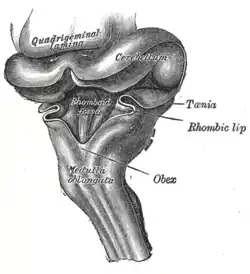

Hind-brain of a human embryo of three months—viewed from behind and partly from left side. (Rhomboid fossa labeled at center.) | |

Rhomboid fossa. | |